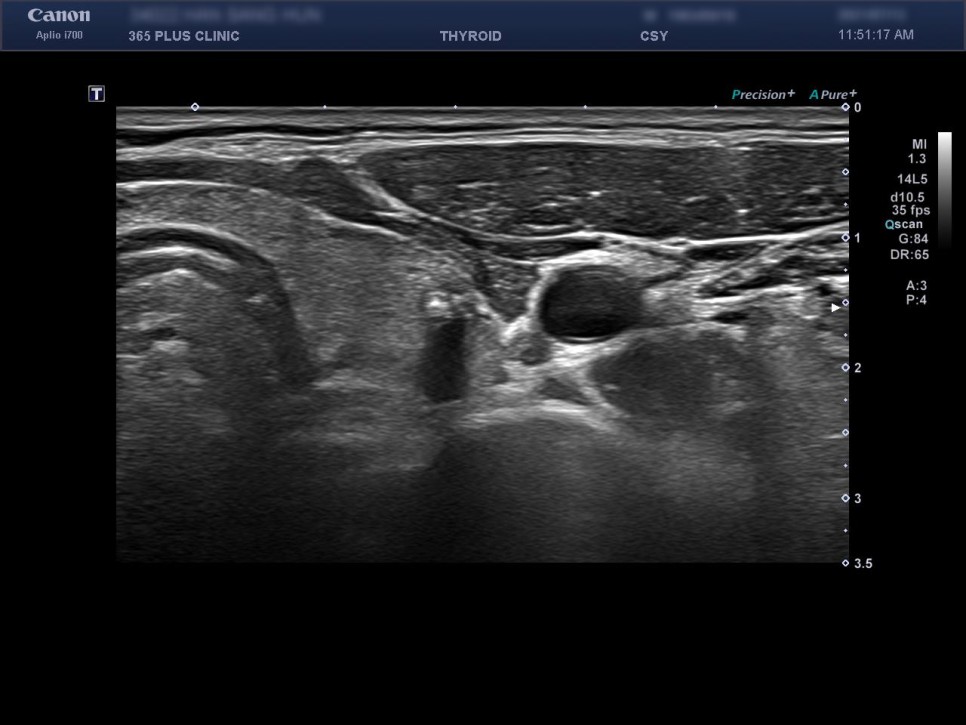

종검 패키지에 포함된 갑상선 초음파 검사에서 갑상선암이 의심되는 병변이 발견되었습니다.

Lt . thyroid nodule

Lt thyroid – mid , 3x3x4mm , K – TIRADS 4 nodule .

2) 갑상선 초음파 검사 [초음파 검사상의 악성을 시사하는 소견]-앞뒤가 긴 편(taller thanwide)-침상(spiculated) 혹은 불규칙한 경계-고형 성분의 현저한 저 에코-미세 및 거대 석회화-경부 림프절 비대의 동반